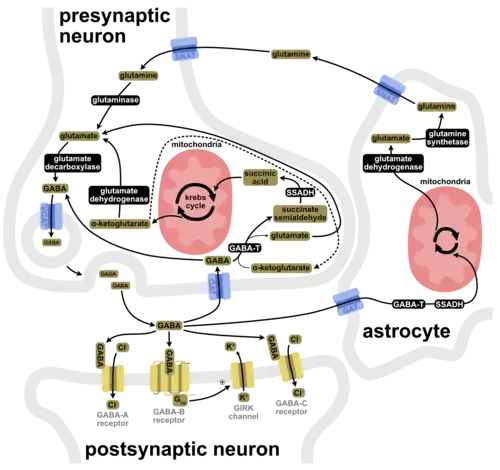

Neurotransmitter

Two general classes of GABA receptor are known:[4]

- GABAA in which the receptor is part of a ligand-gated ion channel complex[5]

- GABAB metabotropic receptors, which are G protein-coupled receptors that open or close ion channels via intermediaries (G proteins)

Neurons that produce GABA as their output are called GABAergic neurons, and have chiefly inhibitory action at receptors in the adult vertebrate. Medium spiny cells are a typical example of inhibitory central nervous system GABAergic cells. In contrast, GABA exhibits both excitatory and inhibitory actions in insects, mediating muscle activation at synapses between nerves and muscle cells, and also the stimulation of certain glands.[6] In mammals, some GABAergic neurons, such as chandelier cells, are also able to excite their glutamatergic counterparts.[7] In addition to fast-acting phasic inhibition, small amounts of extracellular GABA can induce slow timescale tonic inhibition on neurons.[8]

GABAA receptors are ligand-activated chloride channels: when activated by GABA, they allow the flow of chloride ions across the membrane of the cell.[5] Whether this chloride flow is depolarizing (makes the voltage across the cell's membrane less negative), shunting (has no effect on the cell's membrane potential), or inhibitory/hyperpolarizing (makes the cell's membrane more negative) depends on the direction of the flow of chloride. When net chloride flows out of the cell, GABA is depolarising; when chloride flows into the cell, GABA is inhibitory or hyperpolarizing. When the net flow of chloride is close to zero, the action of GABA is shunting. Shunting inhibition has no direct effect on the membrane potential of the cell; however, it reduces the effect of any coincident synaptic input by reducing the electrical resistance of the cell's membrane. Shunting inhibition can "override" the excitatory effect of depolarising GABA, resulting in overall inhibition even if the membrane potential becomes less negative. It was thought that a developmental switch in the molecular machinery controlling the concentration of chloride inside the cell changes the functional role of GABA between neonatal and adult stages. As the brain develops into adulthood, GABA's role changes from excitatory to inhibitory.[9]

Biosynthesis

GABA is primarily synthesized from glutamate via the enzyme glutamate decarboxylase (GAD) with pyridoxal phosphate (the active form of vitamin B6) as a cofactor. This process converts glutamate (the principal excitatory neurotransmitter) into GABA (the principal inhibitory neurotransmitter).[44][45]

GABA can also be synthesized from putrescine[46][47] by diamine oxidase and aldehyde dehydrogenase.[46]

Metabolism

GABA transaminase enzymes catalyze the conversion of 4-aminobutanoic acid (GABA) and 2-oxoglutarate (α-ketoglutarate) into succinic semialdehyde and glutamate. Succinic semialdehyde is then oxidized into succinic acid by succinic semialdehyde dehydrogenase and as such enters the citric acid cycle as a usable source of energy.[48]